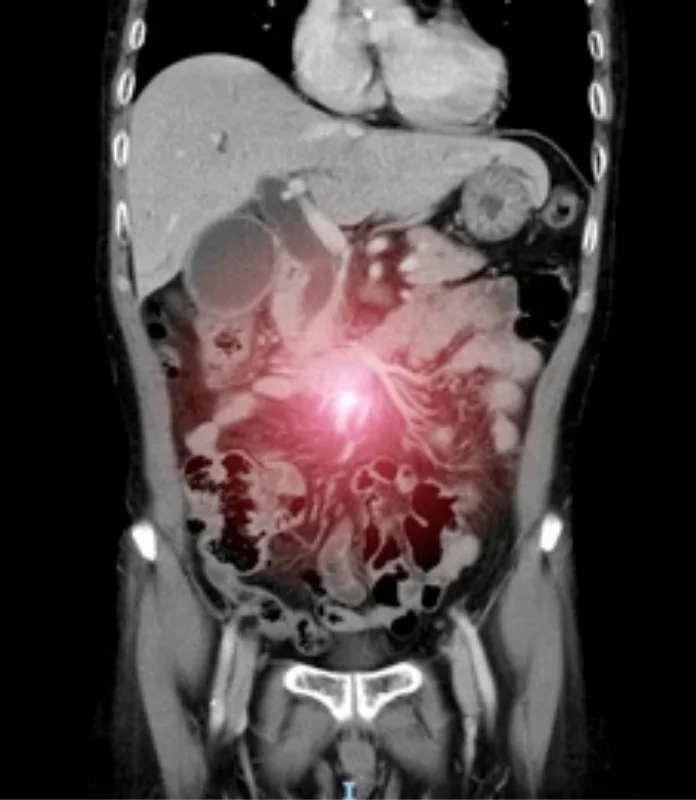

An advanced and highly specialized cancer treatment designed for patients with cancers that have spread to the lining of the abdominal cavity (peritoneum).

Hyperthermic Intraperitoneal Chemotherapy (HIPEC) is an advanced and highly specialized cancer treatment designed for patients with cancers that have spread to the lining of the abdominal cavity (peritoneum). This approach combines extensive tumor-removal surgery with direct, heated chemotherapy delivery, targeting cancer cells at their source. HIPEC allows oncologists to treat peritoneal disease more aggressively and precisely, offering selected patients improved disease control, reduced recurrence risk, and better long-term outcomes compared to systemic chemotherapy alone.

HIPEC is a procedure performed immediately after cytoreductive surgery, during which heated chemotherapy is circulated throughout the abdominal cavity before surgical closure.

Unlike intravenous chemotherapy, HIPEC delivers high concentrations of anticancer drugs directly to the affected surfaces, allowing better penetration into residual microscopic cancer cells while minimizing exposure to the rest of the body.

HIPEC is recommended for carefully selected patients whose cancer is primarily confined to the peritoneal surfaces and can be surgically reduced to minimal disease.